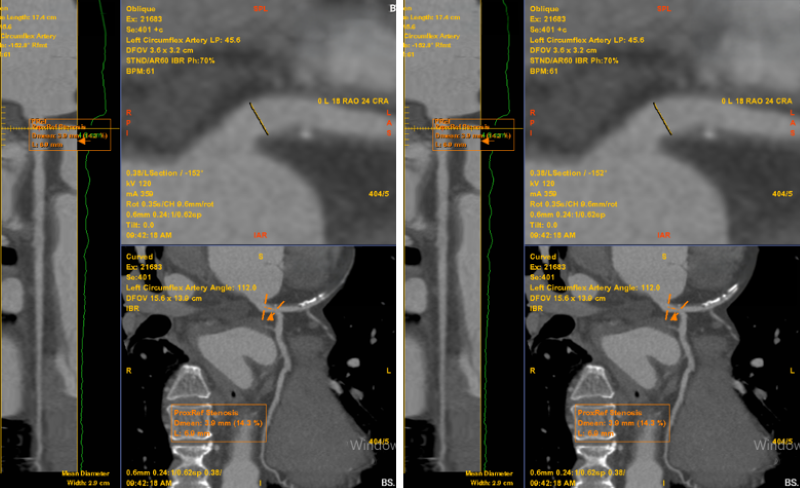

Nhận định cơn đau ngực có nhiều khả năng liên quan đến bệnh lý mạch vành, các bác sĩ đã chỉ định chụp MSCT mạch vành. Kết quả cho thấy bệnh nhân có mảng xơ vữa hỗn hợp gây hẹp khoảng 60–70% đoạn LAD1–2, được phân loại CAD-RADS 3.

Bất thường được phát hiện trên phim chụp MSCT mạch vành của bệnh nhân (Ảnh: Medlatec).